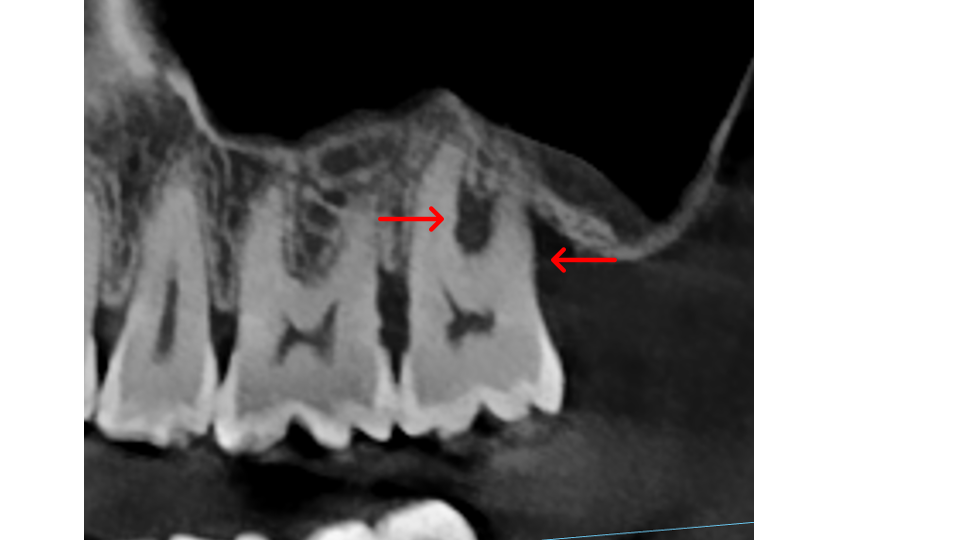

Furcations: This is the area where the roots of a multi-rooted tooth divide. Lower molars have one furcation (two roots); upper molars have three furcations (three roots). When bone loss reaches the furcation, disease spreads through the tooth, not just around it, creating undercuts that trap bacteria and make the area extremely difficult to clean without surgical access.

Bone thickness and shape: Bacteria on your teeth can only cause bone destruction within about 1.5 mm of where they sit, referred to as their "sphere of influence." When the surrounding bone is thin or roots are very close together, bacteria can destroy the bone completely, leading to gum recession and more exposed tooth surface. In these cases, non-surgical therapy is often sufficient. When bone is thick, bacteria can only destroy part of it, creating craters or "moats" around the tooth. These craters cannot be fully cleaned with non-surgical treatment and typically require surgery to correct.

- X-Rays (Radiographs): X-rays show the pattern and extent of bone loss. We can see whether bone has been lost evenly (horizontal loss) or whether craters and vertical defects have formed. This pattern directly determines which type of treatment you need.

Step 4, Osseous Surgery (if needed): For pockets that remain deep, surgery gives us direct access to clean root surfaces and reshape or rebuild bone.